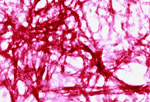

Αμερικανική μελέτη αποκαλύπτει τον τρόπο που συγκεκριμένοι νευροδιαβιβαστές μεταδίδονται και φτάνουνσ τους στόχους εντός του εγκεφάλου, ανοίγοντας έτσι τον δρόμο για νέες θεραπείες του άγχους αλλά και άλλων εγκεφαλικών διαταραχών.